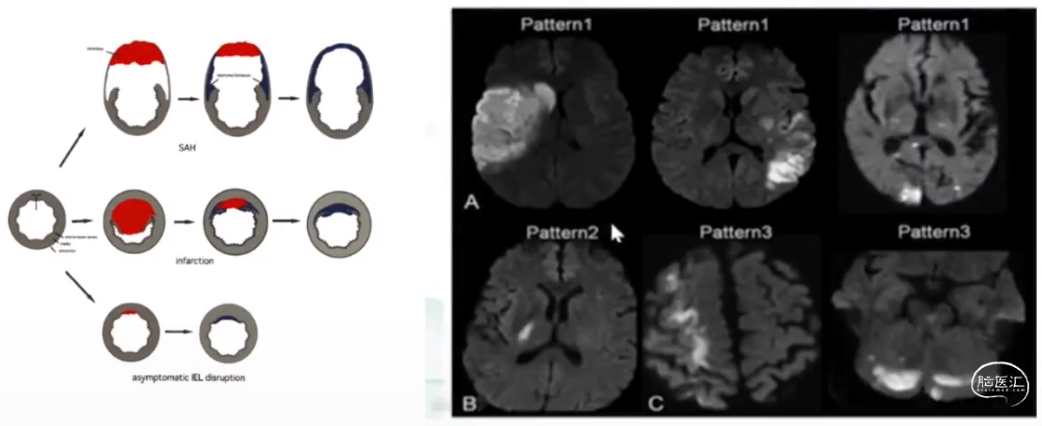

颅颈动脉夹层

·中青年卒中最常见的病因之一

·约占总体人群卒中原因2.5%,青年人卒中原因的20%以上

·颈动脉夹层患者卒中:血栓栓塞性卒中(80%);重度狭窄或闭塞所致低灌注(15%);混合机制(5%)

心源性栓塞

·青年卒中最常见的卒中亚型

·患先天性心脏病的年轻成人(18-55岁),发生缺血性脑卒中的风险是一般人群的9-12倍

·栓塞机制:

-脓毒性:感染性心内膜炎;风湿性心脏病

-非脓毒性:右向左分流(房间隔缺损,卵圆孔未闭);心房粘液瘤;心律失常;心肌病

-其他(空气栓塞;脂肪栓塞)

卵圆孔未闭

·成人中最常见的先天性心脏异常(人群患病率25%)

·出生后,约75%的人卵圆孔自动关闭,而25%的人发生卵圆孔未闭(PFO)。

·导致卒中的诱因

·导致偏头痛的部分原因

·20%-40%的IE会发生神经系统并发症,主要为卒中。

·IE导致的卒中:

-70%为脑梗死和TIA: 70%-90%的颅内栓塞都位于大脑中动脉区域

-30%为脑出血:梗死后出血转化、细菌性动脉瘤破裂、动脉炎血管壁破裂,皮层微出血